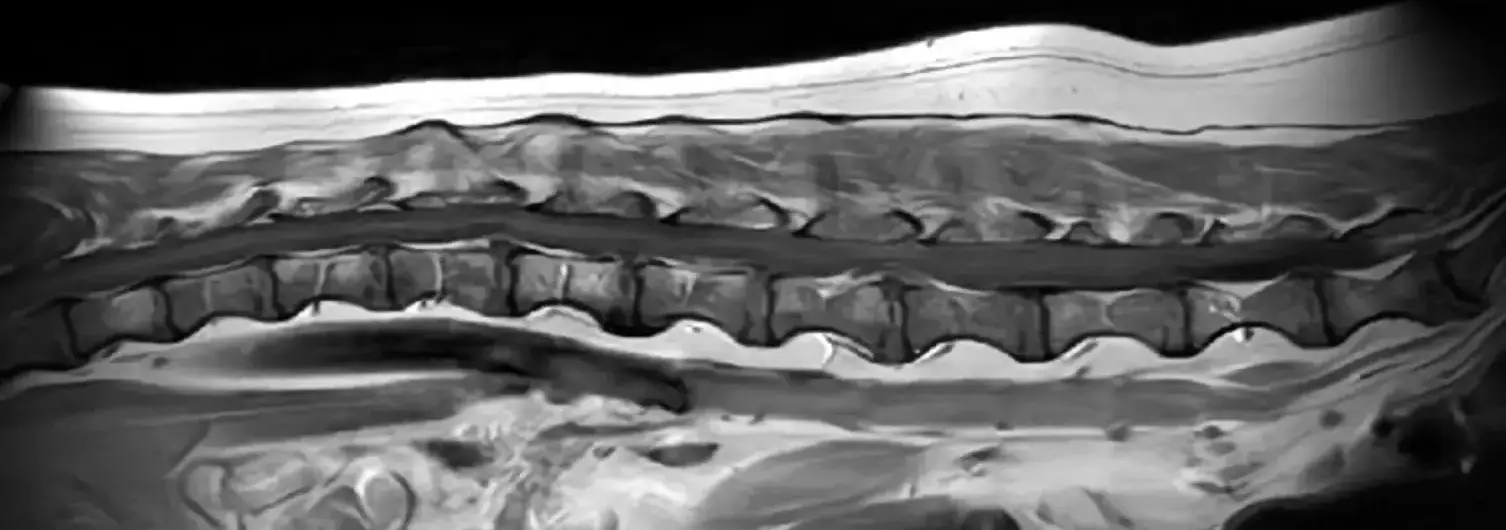

- 神経学的検査:歩行や反射の評価でグレードを判定

- 画像診断:

- MRI:最も確実。脊髄圧迫の程度と部位を確認

- CT:骨や椎間板の突出部位を確認

- 脊髄造影:古くからの方法だが、MRIの方が一般的になりつつある

※CT検査だけでは圧迫部位の予測はついても脊髄の状態がわからないため、明らかな場合以外は単独で診断に用いることはありません。CT、MRI両方撮像できれば理想ですが、費用がネックです。

MRI検査で13~15万円くらい、CT検査も10万円近くします。

最も一般的な手術は「片側椎弓切除術(hemilaminectomy)」です。背骨の一部を削り、飛び出した椎間板物質を除去します。

外部医療機関でMRIを撮像してきてもらい、その画像を元に外科手術を計画します。